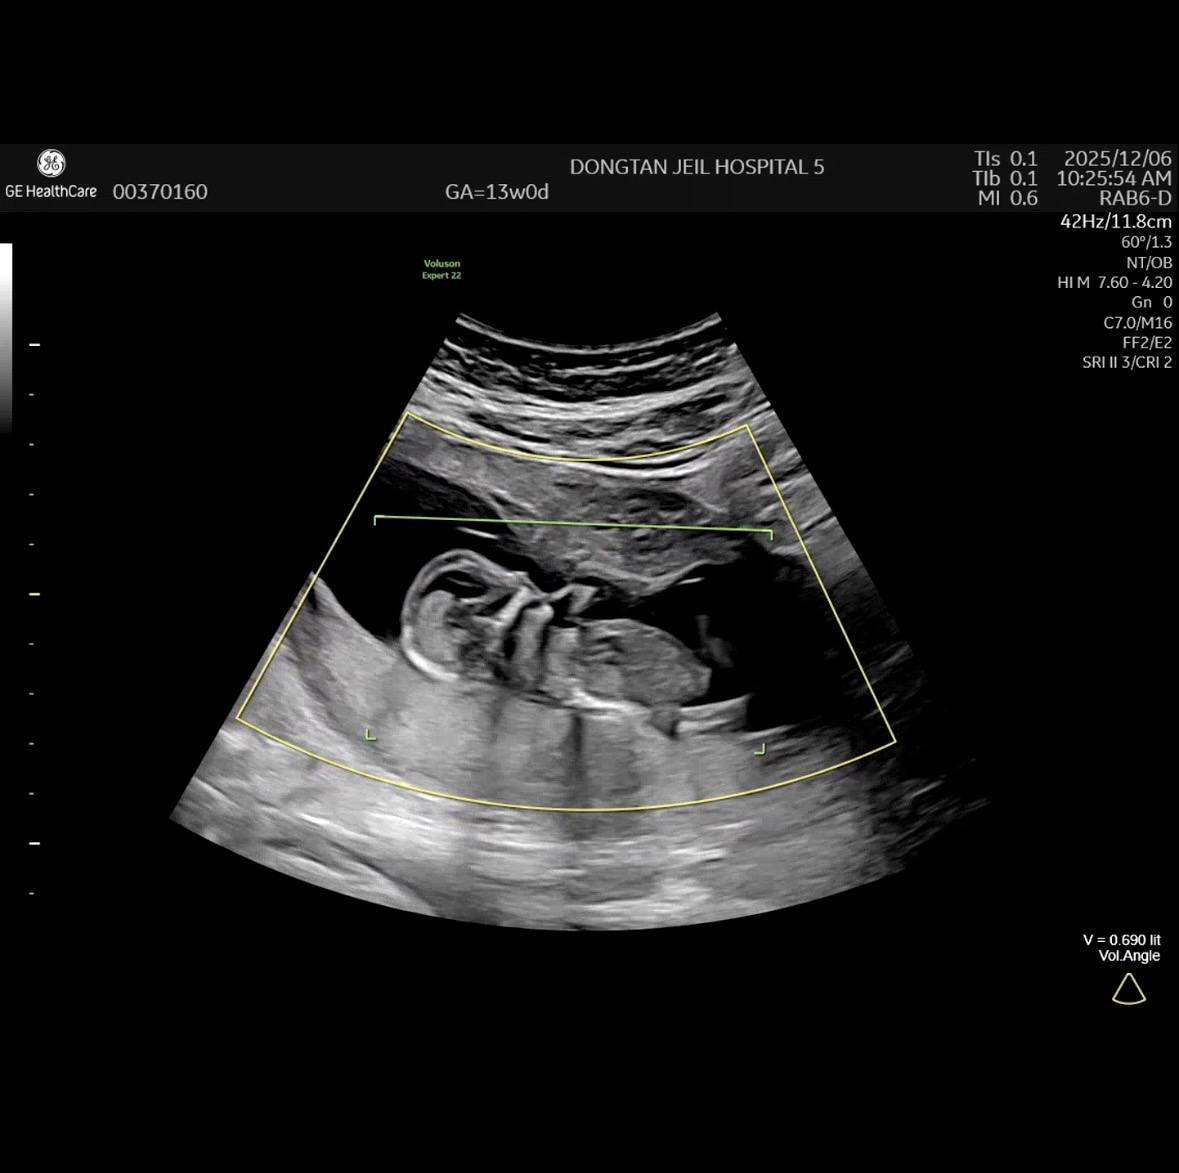

13주 0일 각도법 문의드려요..!

너무너무 궁금해서 여쭤봐요! 제가 각도법 볼줄을 아예 몰라서ㅜㅜ 투표해주시면 감사드리겠습니다🥹